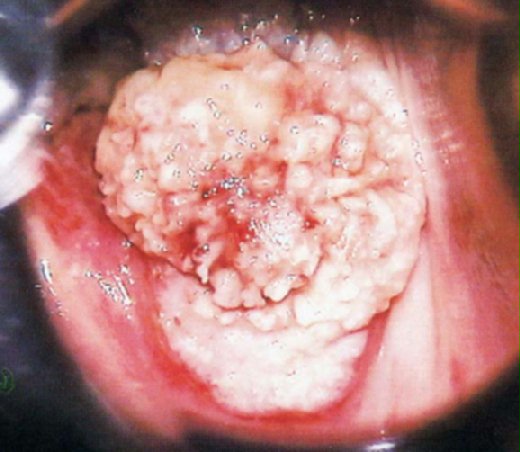

↓下圖一為女性菜花,圖二為男性菜花。